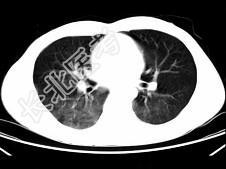

- 单项选择题男,35岁, 被车撞伤后1小时,结合影像图像选择其最可能的诊断为 ( )

D、肺挫伤